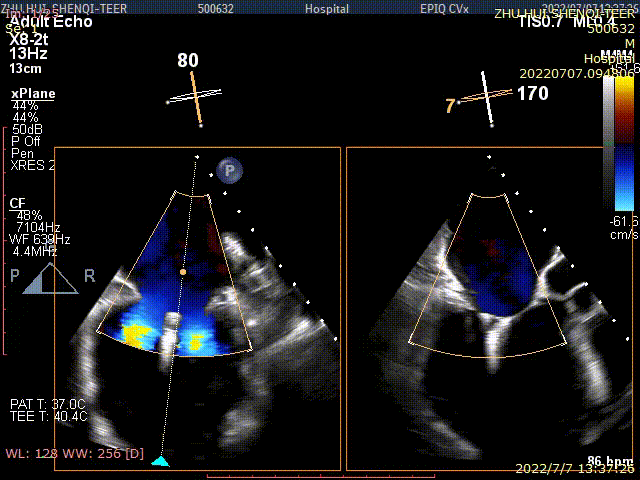

术后TEE显示,二尖瓣双孔化形成,反流明显减少